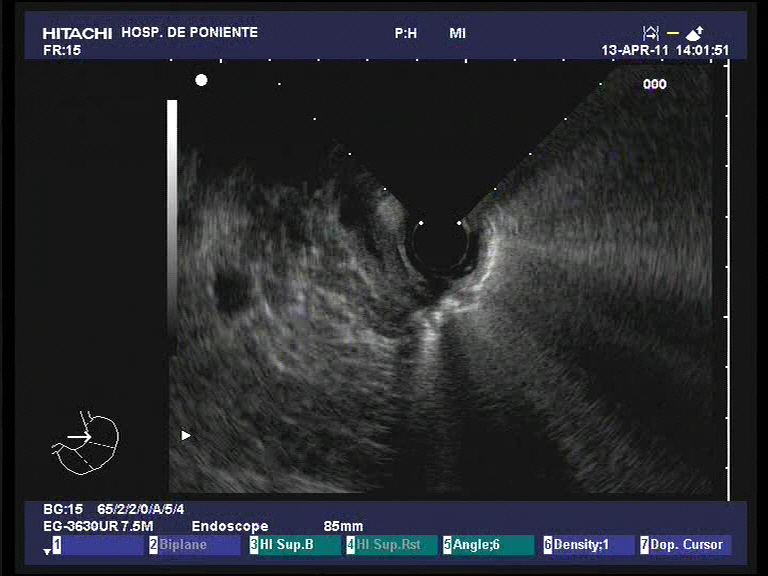

Colangiocarcinoma extrahepático distal: diagnóstico por ecoendoscopia, CPRE y colangioscopia (Spyglass)

Las estenosis indeterminadas biliares, como se ha comentado en otros casos publicados en este blog, constituyen un reto diagnóstico para el gastroenterologo biliopancreático. En ocasiones, incluso realizando todos los métodos de imagen a nuestro alcance (ECO, TAC, USE, CPRM, CPRE..) el diagnóstico sigue sin aclararse. Ultimamente disponemos de una herramienta más que nos puede ayudar a solventar dicho problema. Se trata de la colangioscopia Spyglass. Con este método complementario de la CPRE de un solo operador, podemos obtener imágenes muy sugerentes de malignidad y sobre todo tomar biopsias dirigidas de las lesiones. Se presenta el caso de un paciente de 72 años al que tras realizarle una ecoendoscopia radial y una CPRE con colangioscopia, se llega a esta conclusión diagnóstica. Desgraciadamente esta técnica, en estenosis distales de la vía biliar (como nuestro caso) es dificil de manejar cuando se usa el forceps de biopsias (Spybite) y en el caso de este paciente, no fueron del todo dirigidas, por lo que el resultado histológico fue inespecífico. No obstante, cuando uno se encuentra con imágenes tan sugerentes, la correlación con los hallazgos de la pieza quirúrgica son bastante altos.